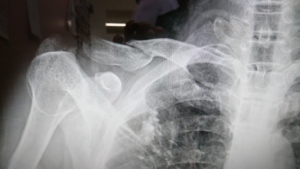

訪問時にその話をしていると、健先生が『昨日の鎖骨骨折の症例をお見せしましょう』とレントゲンを見せてくれた。